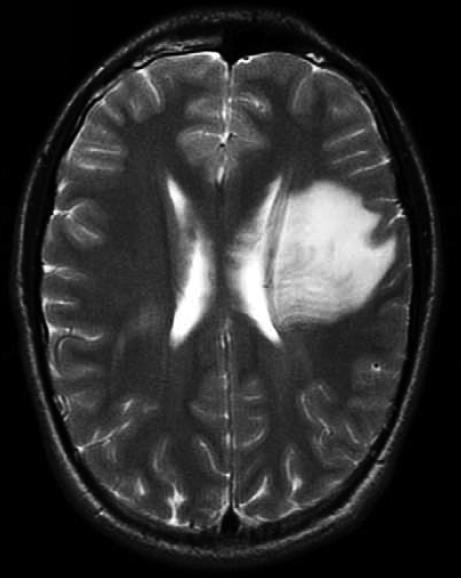

• 肿瘤样脱髓鞘病变报道3例

2023, 48(5):614-617. DOI: 10.13406/j.cnki.cyxb.003183

摘要 (95) HTML (24) PDF 1.29 M (241) 评论 (0) 收藏

摘要: